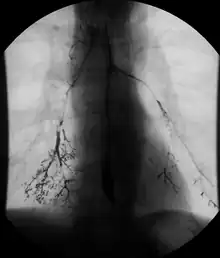

Enteroclysis

Enteroclysis is also known as small bowel enema.[21] It has been largely replaced by magnetic resonance enterography/enteroclysis[13] and computed tomography enterography/enteroclysis.[22]

In addition to fasting for 8 hours prior to examination, a laxative may also be necessary for bowel preparation and cleansing.[12] The main aim of this study is to distend the proximal bowel through infusion of large amount of barium suspension. Otherwise, the distension of distal small bowel is generally similar with small bowel follow-through. Therefore, there is a need to pass a tube through the nose into the jejunum (nasojejunal tube) to administer large amount of contrast. This can be unpleasant to the subject, requires more staff, longer procedural time, and higher radiation dose when compared to small bowel follow-through. The indications for enteroclysis are generally similar to small bowel follow-through. Barium suspensions such as diluted E-Z Paque 70% and Baritop 100% can be used. After that, 600 ml of 0.5% methylcellulose is administered after 500 ml of 70% barium suspension is given. Bilbao-Dotter tube and Silk tube can be used to administer barium suspension. The subject should be fasted overnight, any antispasmodic drugs should be stopped one day before the examination, and Tetracaine lozenges can be used 30 minutes before the procedure to numb the throat for nasojejunal tube insertion.[13]

The filling of the small intestines can be viewed continuously using fluoroscopy, or viewed as standard radiographs taken at frequent intervals. The technique is a double-contrast procedure that allows detailed imaging of the entire small intestine. However, the procedure may take 6 hours or longer to complete and is quite uncomfortable to undergo.[23]

- Enteroclysis has shown to be very accurate in diagnosing small bowel diseases, with a sensitivity of 93.1% and specificity of 96.9%. It permits detection of lesion which may not be seen with other imaging techniques.[7] There is no significant difference in terms of detection of clinically significant findings, sensitivity or specificity between enteroclysis and CT enterography.[1] Enteroclysis compares favorably with wireless capsule endoscopy and double-balloon endoscopy in the diagnosis of mucosal abnormalities of the small bowel.[24]